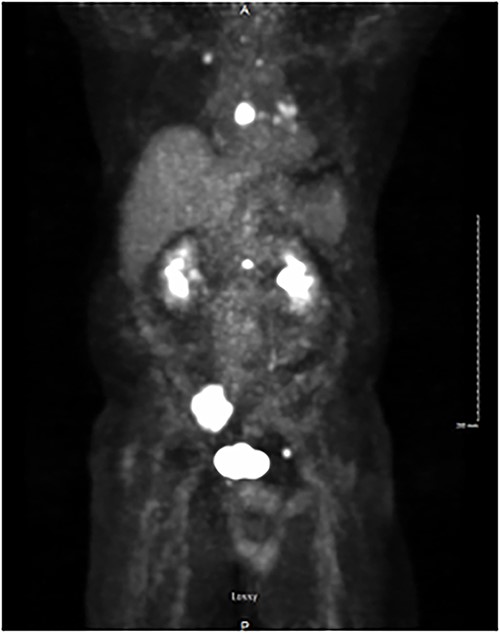

A total of 6 weeks after surgery, while preparing for postoperative radioactive iodine therapy (RAI), the patient developed right hip pain and leg numbness. MRI of the lumbar spine revealed a 5.0 × 4.6 cm expansile lesion in the right sacroiliac joint (SI) and a herniated disk at L3-L4 (Fig. 3). CT-guided core biopsy of the mass confirmed metastatic PTC. He was treated with 165 mCi of I-131 and subsequent whole-body scan (WBS) showed uptake in the neck, right SI joint, and the posterior mediastinum. A positron emission tomography (PET-CT) scan demonstrated 18F-fluorodeoxyglucose (FDG)-avid mediastinal and left hilar adenopathy with no residual disease in the head and neck (Fig. 4). The patient was then treated with external beam radiation therapy with 40 Gy to the sacrum in 20 fractions. He was started on zoledronic acid, dabrafenib, and trametinib, but later switched to lenvatinib when follow up imaging showed persistent metastases. At 36 months following surgery, the patient remains on lenvatinib with PET-CT evidence of new peritoneal carcinomatosis and stable osseous metastases.

PET/CT demonstrating isotope uptake indicative of metastatic disease. Coronal section demonstrating no evidence of neoplastic disease in the head and neck region. Several foci of metastatic disease are present at the level of thoracic inlet. Shown are a 5 cm lytic metastatic focus involving R sacrum, 1.5 cm isotope positive focus of lytic metastatic disease involving the mid-portion of the sternum, and smaller positive foci involving left side of body of L-1, anterior aspect of left acetabulum, posterior aspect of 7th left rib, medial aspect of right clavicle and left transverse process of T-1.